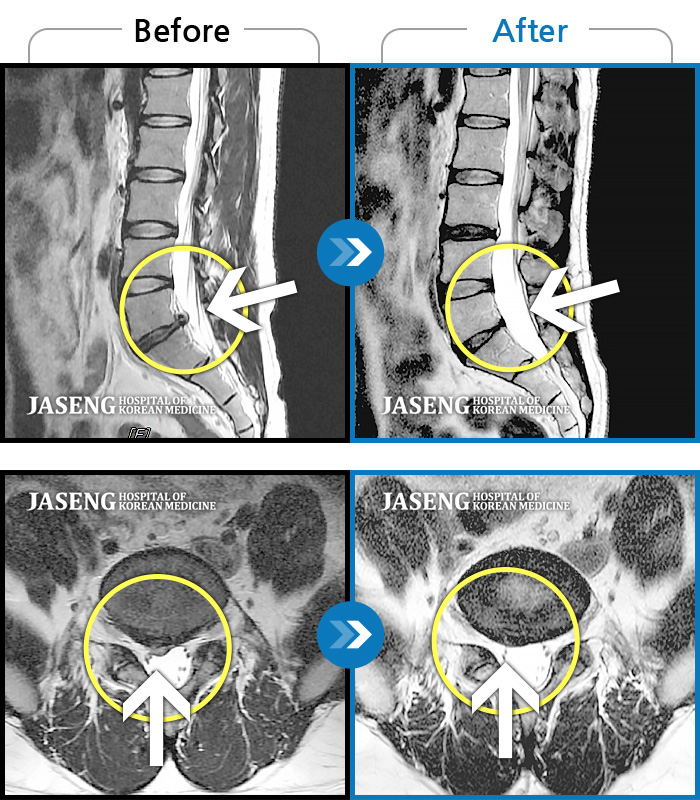

허리디스크

도움받은 사례

강남 · 강만호 원장

허리통증이 심해서 숙이기 어렵고 차에서 내리기 힘들었습니다.

촬영시기

2021.01.06 ~ 2025.03.10

2025.03.20

조회수 13,020